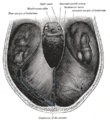

Brain human normal inferior view with labels en.svg

Inferior view of the human brain, with the cranial nerves labelled.